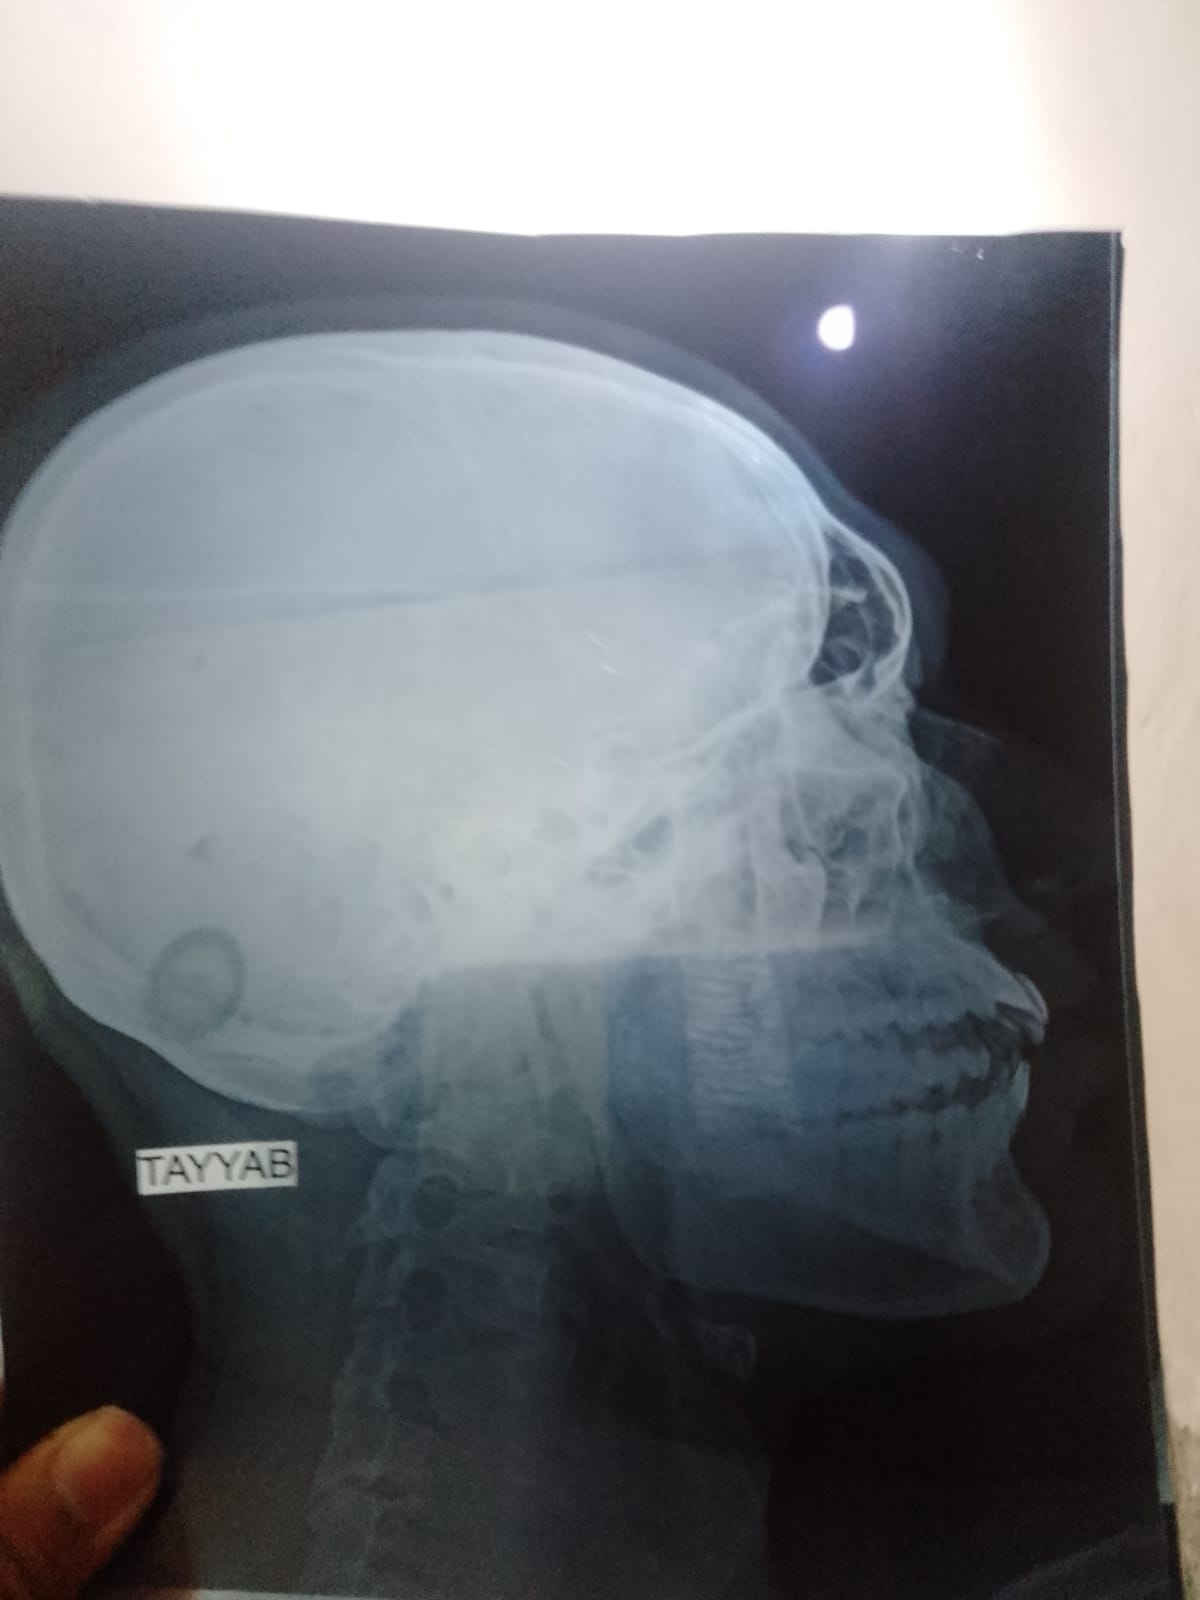

mera 7 din phly accident hua tha or meri nakk sy bohat bleeding hoi or osi din sy meri ankh k nechy jo hadii wo thori tot gi hy my apna pori trha moh ni khol skta ab na kuch kha paa rha hu mayoo hospital walo ny mjy operation ka kaha hy k ap operation krwa lo mey yeh pochna tha k yeh chez bina operate hove thk ni hoskti kya or agr operate he hona hhy to wo kis trha hoga mtlb k cuts lgygy face kya orr hadii face ke kesyy shi hogi please esky bary my mjy guide krdy

Aoa,apko left ZMC (Mid face) fracture hai.Ye baghair operation theek nai Hoga.You should follow what Mayo hospital surgeons have said

face symmetry cannot be corrected without surgery. secondly we do the most cuts from inside the mouth and one or two minor cuts on face which is hidden under eye brow. so no

need to worry about that

salam

yes it needs to be operated.

some incisions are made on the face but they are hidden once healed.

plates lagai jati hain take haddi sahi jaga jur jaye.

khud se sahi ni hoga operation zaroori hai